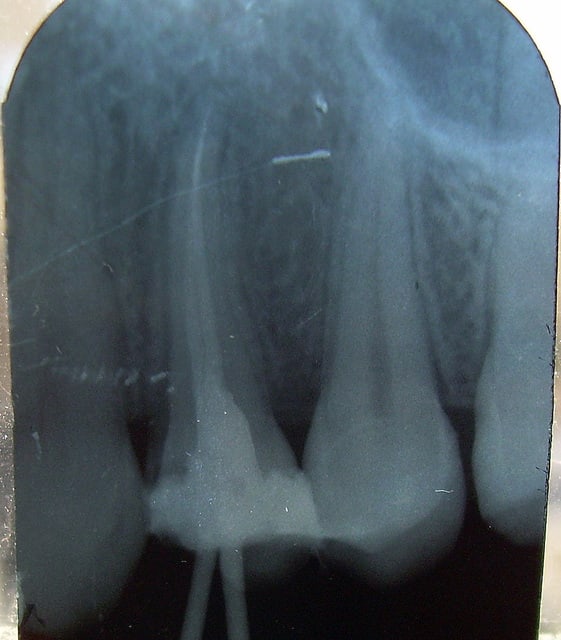

VOILA LES RADIO, celle pre op et lime en place pour la LT n y sont pas (restees au cab),la verif c est celle prise quand j ai senti que ca coincait a l apex du canal vestibulaire, la derniere c est avant de couper les cones. Avec du recul, j aurai du faire une radio defilee pour dissocier mes 2 canaux, mais bon...